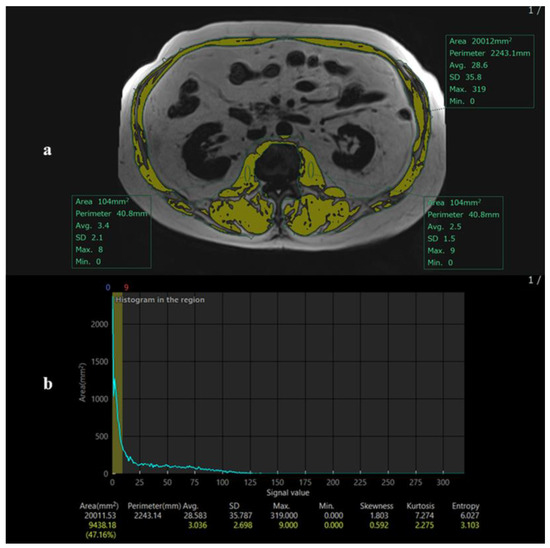

Due to variability in scan ranges, the L2 level was chosen instead of L3, which was not consistently captured. Previous studies, including Wang et al. [9], have demonstrated strong correlations between skeletal muscle area measured at L2 and the conventional L3 level, supporting the validity of this approach. The maximal psoas muscle region was identified, and skeletal muscle area was segmented automatically using intensity-based thresholding (Figure 2). A single observer performed measurements.

Figure 2.

Method for extracting the values of the cross-sectional area for skeletal mass index (L2SMI). (a) The method for extracting the values of the cross-sectional area for skeletal mass index (L2SMI) using the 2-point DIXON technique. A circular region of interest (ROI) with an area of 120 mm2 is defined within the muscle area that has the highest density, typically the psoas muscle. This ROI is placed in the muscle region of a fat image. The signal intensity within this circular ROI is analyzed. The maximum signal intensity value within the ROI is used as a threshold. Regions within the fat image with signal intensities below the defined threshold are automatically extracted. (b) The histogram of the same patient (a).

Skeletal muscle index (L2SMI) was calculated as muscle area divided by height squared (cm2/m2) [9]. Sarcopenia was defined as L2SMI < 42 cm2/m2 for men and <38 cm2/m2 for women, based on the Japanese Liver Society guidelines [10].